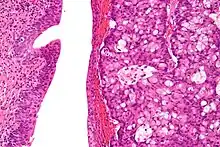

High magnification micrograph of a urachal carcinoma. H&E stain

The urachus is also subject to neoplasia. Urachal adenocarcinoma is histologically similar to adenocarcinoma of the bowel. Rarely, urachus carcinomas can metastasise to other regions of the body, including pelvic bones and the lung.[7]